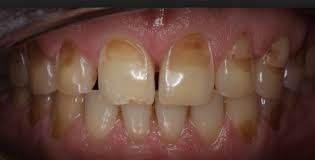

Discoloration. As the enamel erodes and more dentin is exposed, the teeth may appear yellow.

Cracks and chips. The edges of teeth become more rough, irregular, and jagged as enamel erodes.